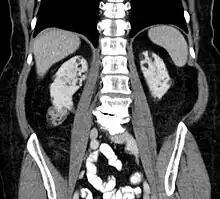

Kidneys

Between 26% and 80% of TSC patients have benign tumors of the kidneys called angiomyolipomas, with hematuria being the most frequent presenting symptom. [9] TSC angiomyolipomas differ from non-TSC angiomyolipomas in age of presentation (31.5 years vs 53.6 years), mean tumor size (8.2 cm vs 4.5 cm), and percentage of cases requiring surgical intervention (50% vs 28%).[9] Although benign, an angiomyolipoma larger than 4 cm is at risk for a potentially catastrophic hemorrhage, either spontaneously or with minimal trauma.